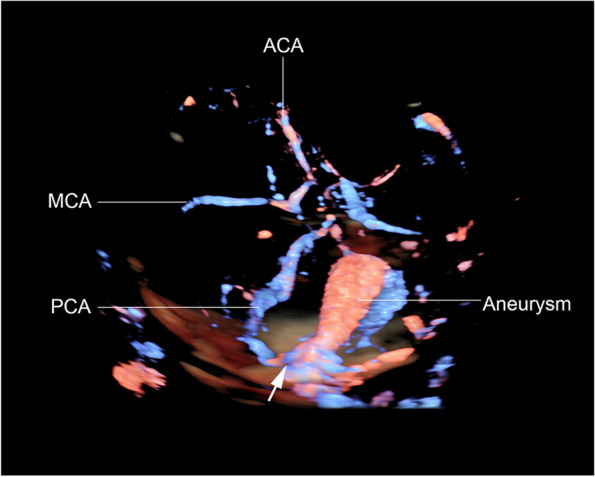

Fig. 3.

Rendered 3D-color flow ultrasound of the fetal brain at 36 weeks of gestation shows course of posterior cerebral artery (PCA) feeding the aneurysm from lateral wall of parieto-temporal hemisphere (arrow: indicating originating point of flow jet feeding the aneurysm). (ACA: anterior cerebral artery; MCA: middle cerebral artery)